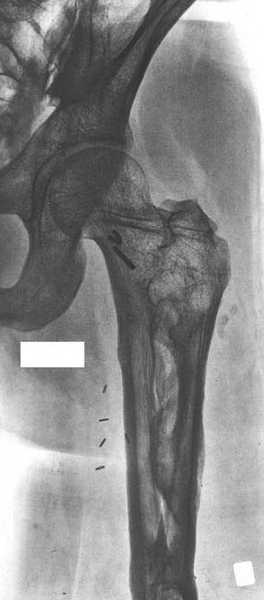

Елена,

При наличии в института сосудистых хирургов, как альтернативный метод можно было бы предложить графт как показано на снимке.

Не мой случай, но красиво!